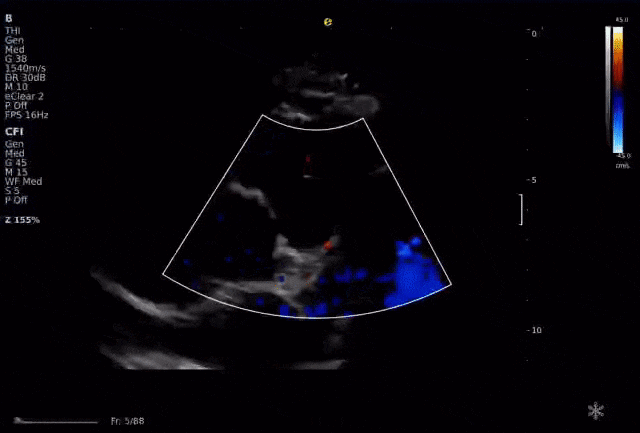

以下为逸超医疗(ESI)设备采集的冠脉图像,清晰展示了其在二维成像、彩色多普勒及频谱多普勒方面的表现:

左右滑动查看更多

心脏冠脉超声